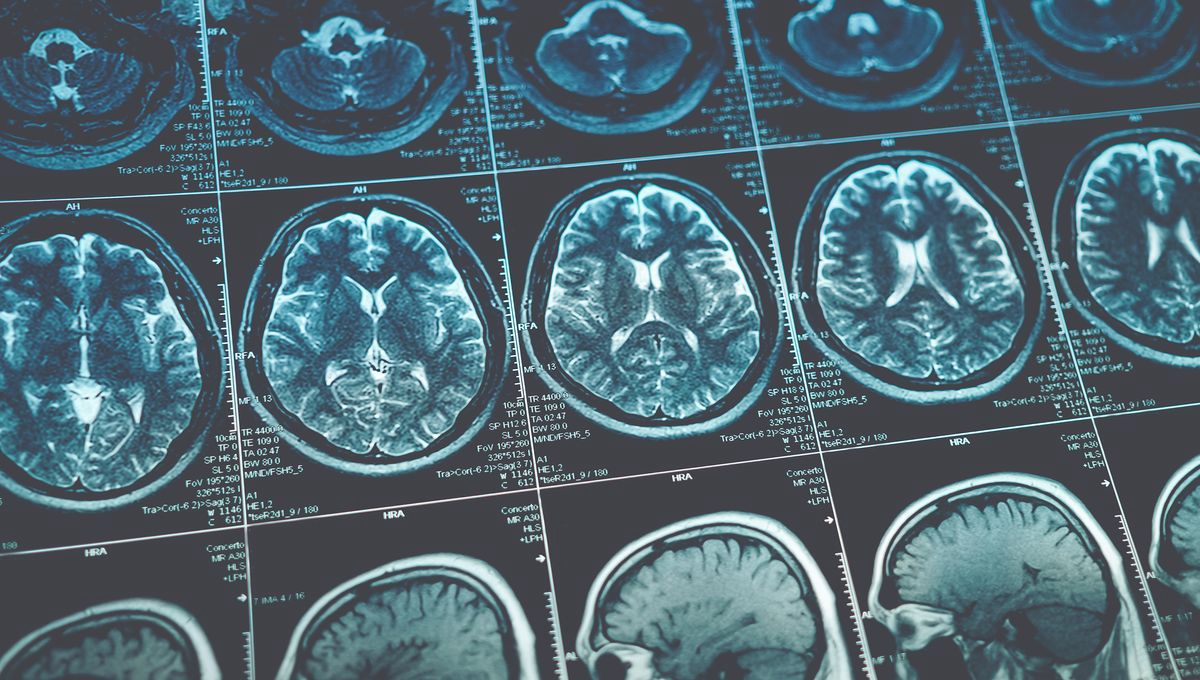

Over 6,000 Scans Reveal What ADHD Looks Like In The Brain

Data from thousands of kids has been used to map connectivity patterns in the ADHD brain.